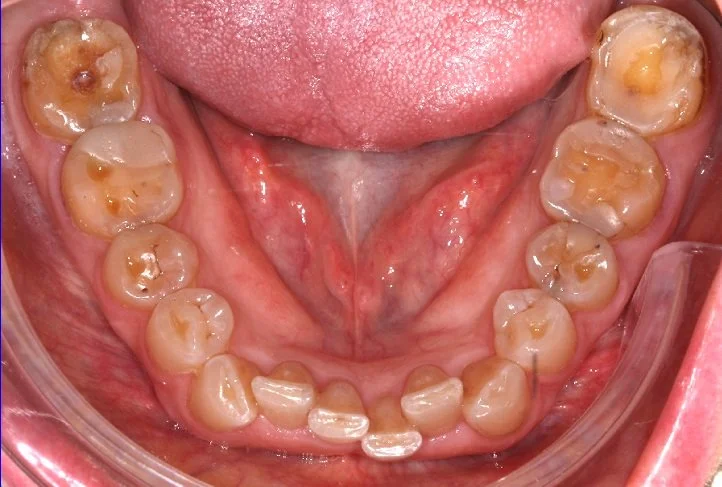

AFFOLLAMENTO INFERIORE

BEFORE

Caso di affollamento e disallineamento dei denti dell’arcata inferiore. Con una serie di allineatori trasparenti, si è ottenuto un ottimo allineamento dentale.